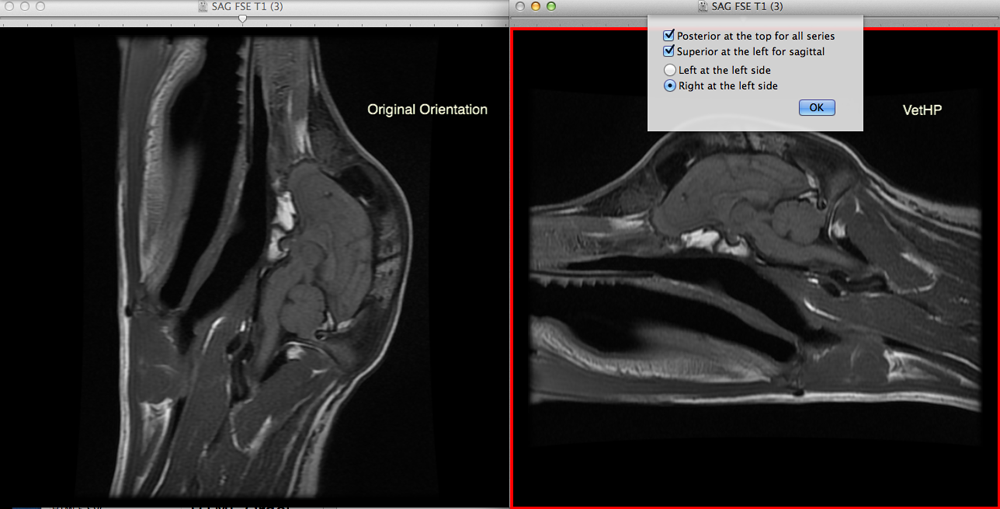

Description: Orient your veterinary CT and MRI images automatically! The Veterinary Hanging Protocol plugin (VetHP) is designed to orient veterinary CT and MRI studies in the way that veterinarians prefer to see them, without adjusting each series by hand. There are three options available to automatically orient transverse, sagittal, and dorsal images consistently, regardless of the scanner used:

Screenshot: